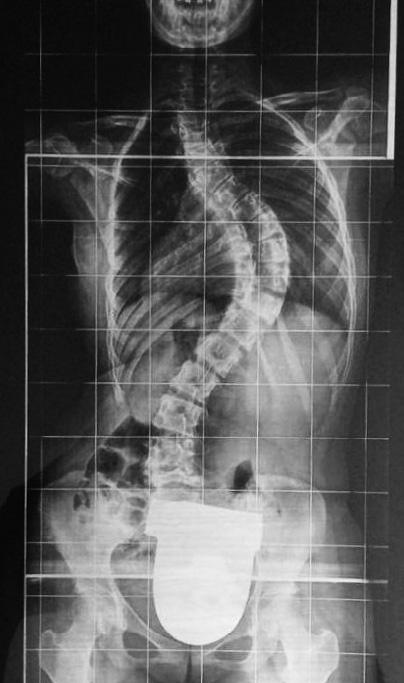

RAGAZZINA CON SCOLIOSI GRAVE: INTERVENTO AL MEYER DI FIRENZE

Il dottor Konstantinos Martikos e la dottoressa Lucrezia Leggi della Chirurgia Vertebrale diretta dal prof. Alessandro Gasbarrini hanno operato all’ospedale pediatrico Meyer di Firenze una quattordicenne colpita da una grave forma di scoliosi, che rischiava di portarla nel giro di poco tempo a una gravissima forma di invalidità perché la colonna vertebrale deformata sarebbe arrivata a premere pericolosamente contro organi vitali.

L’intervento, durato quasi otto ore, ha visto l’applicazione di barre e viti speciali per raddrizzare la colonna e accompagnarla nella crescita. Il recupero, con quattro centimetri di altezza in più, è stato del cento per cento e dopo la riabili-

tazione la paziente, che risiede a Pontasserchio, frazione del comune di San Giuliano Terme in provincia di Pisa, potrà avere una vita perfettamente normale.

L’intervento è stato reso possibile dall’accordo siglato tra il Rizzoli e il Meyer il 19 dicembre 2021, che permette a queste due realtà di eccellenza di collaborare in modo continuativo per poter offrire ai piccoli pazienti e alle loro famiglie una risposta super specialistica nel campo dell’ortopedia pediatrica.

colleghi del Rizzoli specializzati nel trattamento di casi complessi di scoliosi.

La chirurgia vertebrale della scoliosi, tra le patologie più insidiose per gli adolescenti sulla quale il Rizzoli ha una scuola di lunga tradizione, è uno degli ambiti su cui gli specialisti di entrambi gli ospedali lavorano insieme per mettere a punto percorsi assistenziali condivisi. In questo caso la ragazzina era stata indirizzata, dopo una prima visita per una postura scorretta nel camminare, all’équipe di Ortopedia del Meyer diretta dal prof. Giovanni Beltrami, che ha interessato i

La vicenda è stata raccontata alla stampa toscana dal nonno della paziente, esprimendo “riconoscenza eterna” verso l’équipe che ha operato la nipote per le “straordinarie doti di competenza e professionalità unite a semplicità, modestia e affabilità”.